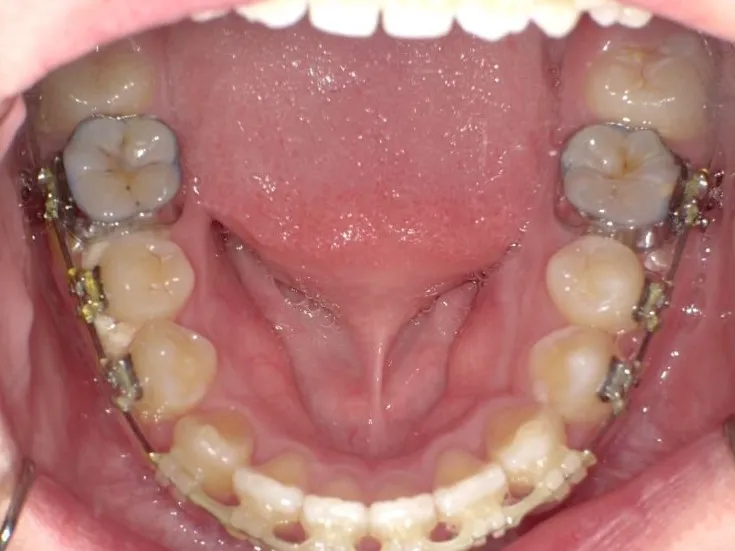

治療終了後

治療回数42回、3年1ヶ月の治療期間で矯正治療を終了しました。

主訴が改善され、ご満足頂きました。

正中のすき間については保定期間にも調整しています。